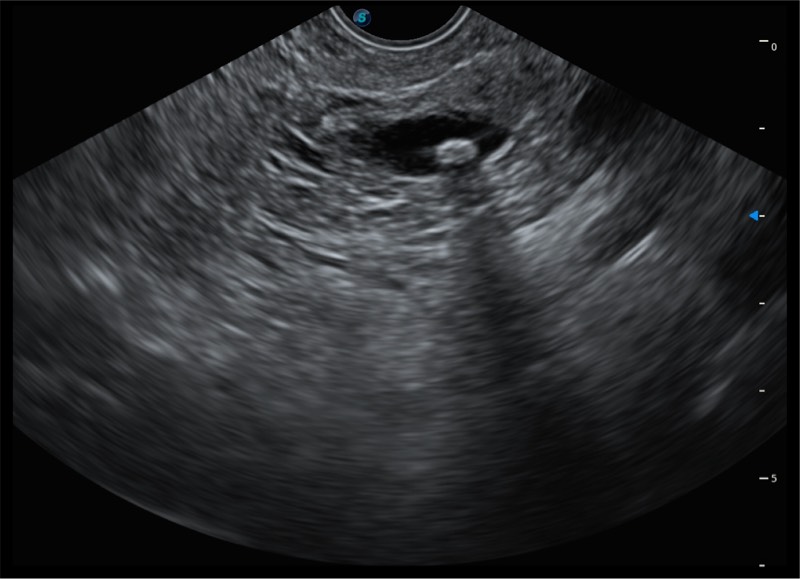

搭载百万级CMOS成像技术

及自主研发凸阵换能器,

可呈现优质的内镜和超声画面

基于二十年的超声技术积累,环球UG官网提供了最新一代的独立超声主机,在提供高质量图像的同时满足多学科使用。具备常见多普勒技术并提供弹性成像、声学造影等高端影像技术。新一代传感器具有更强的抗干扰能力并减少图像伪影。

4.0mm大钳道

12.6mm先端部外径

150°超声扫描角度